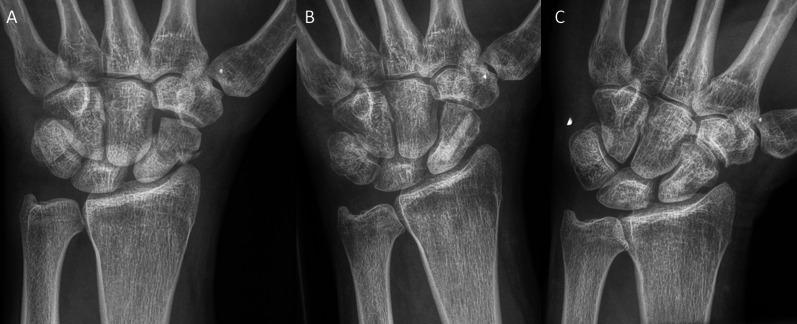

异体皮质骨螺钉治疗舟状骨骨折和假关节。一项多中心回顾性研究。

Treatment of scaphoid fractures and pseudarthroses with the human allogeneic cortical bone screw. A multicentric retrospective study.

Allograft bone screws are rarely described for the fixation of the scaphoid. When fresh fractures are treated, metal screws are mainly used; when pseudarthrosis is the indication, plates in combination with vascularized or non-vascularized bone grafts are mainly used. The necessity of metallic screw removal is under debate, but it is mandatory for plates because of movement restrictions due to the plate. The use of biomaterials in scaphoid fracture fixation was described as leading to union rates of between 64 and 100%. Brcic showed the incorporation of an allogeneic cortical bone screw at 10 weeks postoperative, along with revascularization and stable osteosynthesis with primary bone healing, without any signs of immunological rejection. The purpose of this retrospective study was to explore the results obtained using an allogenic cortical bone screw (Shark Screw®) in patients with fresh scaphoid fracture fixation and pseudarthroses with respect to union rates and time to union.

We retrospectively analyzed 75 patients: 31 with fresh fractures and 44 pseudarthrosis patients. The Shark Screw® was used for the fixation of the scaphoid in the fresh-fracture and pseudarthrosis patients. We evaluated the union rate, complication rate and time to union.

Using the human allogeneic cortical bone screw for scaphoid fracture fixation led to a high union rate (94-96%). There were two nonunions in the fresh fracture group and two nonunions in the pseudarthrosis group. The complication rate was 1.3% (1 patient). Median time to union was 16, 18 and 29 weeks for the fresh-fracture, pseudarthrosis and delayed-union patients, respectively. The treatment of fresh scaphoid fractures and pseudarthroses showed similar union rates to those described in the literature, uses a shorter and less invasive surgical method with no need for hardware removal, and has a low complication rate.

Using the human allogenic cortical bone screw (Shark Screw®) led to similar union rates in fresh fractures-but better union rates in pseudarthrosis patients-compared to those presented in the literature for other scaphoid fracture fixation techniques, and it enabled a short and low-invasive procedure without any donor site morbidity and without the necessity to remove the hardware in a second surgery. The pseudarthrosis patient group showed a particularly strong benefit from this new procedure. The physiological bone metabolism remodels the cortical bone screw without scars.